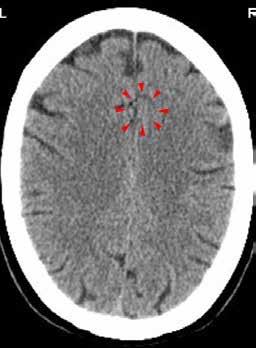

Zobje in telesni organi

Na sliki desno je shema povezav med zobmi in telesnimi organi, ki so jo naredili na Dr. Clark Research Slovenija (Drclark. si) po izsledkih več tisočletij starih spoznanj tradicionalne kitajske medicine. Denimo, levi zgornji modrostni zob (št. 28) je povezan z meridianom tankega črevesa in srca. Zaradi bolnega zoba in zatorej motenega pretoka čija čez ta meridian imamo lahko migrene, epilepsijo, težave s srednjim ušesom, rameni, komolcem, možgani, hrbtenjačo, krvjo, venami in arterijami. Njihova še podrobnejša shema, ki je dostopna na misteriji.si/blog/cat/pomoc_ pri_zdravju/, pa razkriva, da lahko to izzove tudi vremensko občutljivost, vremenski glavobol, mišično distonijo (krčenje mišic), multiplo sklerozo, možganski tumor, motnje vitalnosti, izostanek glasu po daljšem govoru, išias, glavobole, zvonjenje v ušesih, zamrznjeno ramo, vnetje obraznega živca, vnetje vidnega živca. Če je ta zob mrtev, pa so težave še toliko hujše.